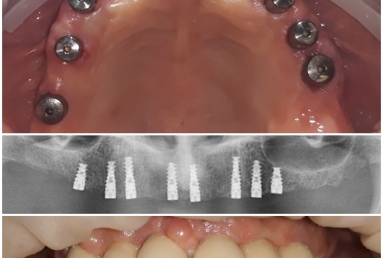

Our patient had advanced periodontal disease with general tooth mobility.

All teeth needed to be extracted and replaced with dental implants. Mobile prothesis were used as temporary restorations.

After implant healing, fixed bridges were made out of porcelain fused to metal.

One more dental implant is needed, but with sinus lift graft, intervention that is postponed for the moment.